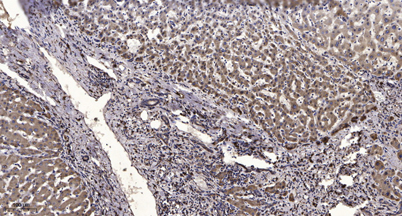

Product name: KCNH1 rabbit pAb

Dilutions: WB 1:500-2000;IHC-p 1:50-300; ELISA 2000-20000

Immunogen: The antiserum was produced against synthesized peptide derived from human KCNH1. AA range:720-769

Cellular localization: Cell membrane ; Multi-pass membrane protein . Nucleus inner membrane ; Multi-pass membrane protein . Cell projection, dendrite . Cell projection, axon . Cell junction, synapse, presynaptic cell membrane . Perikaryon . Cell junction, synapse, postsynaptic density membrane . Early endosome membrane . Perinuclear KCNH1 is located to NPC-free islands.

Background: Voltage-gated potassium (Kv) channels represent the most complex class of voltage-gated ion channels from both functional and structural standpoints. Their diverse functions include regulating neurotransmitter release, heart rate, insulin secretion, neuronal excitability, epithelial electrolyte transport, smooth muscle contraction, and cell volume. This gene encodes a member of the potassium channel, voltage-gated, subfamily H. This member is a pore-forming (alpha) subunit of a voltage-gated non-inactivating delayed rectifier potassium channel. It is activated at the onset of myoblast differentiation. The gene is highly expressed in brain and in myoblasts. Overexpression of the gene may confer a growth advantage to cancer cells and favor tumor cell proliferation. Alternative splicing of this gene results in two transcript variants encoding distinct isoforms. [provided